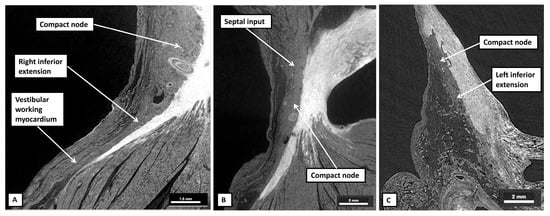

3.4. The Histological Make-Up of the Atrioventricular Node

3.8. The Substrates for Atrioventricular Nodal Re-Entry Tachycardia

3.9. The Species Variability in the Morphology of the Atrioventricular Node